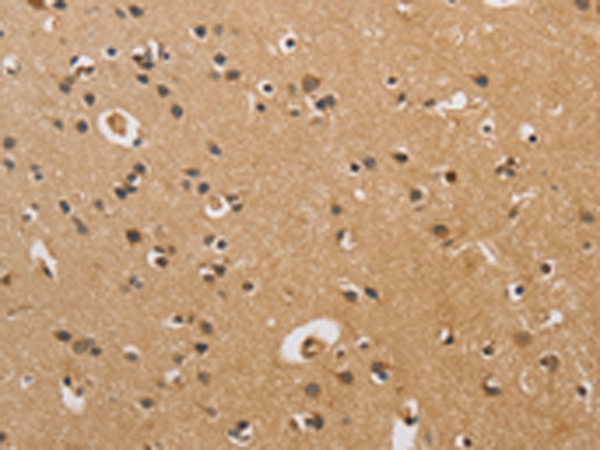

分类: 科研抗体货号: P08199别名:应用: IHC反应种属: Human